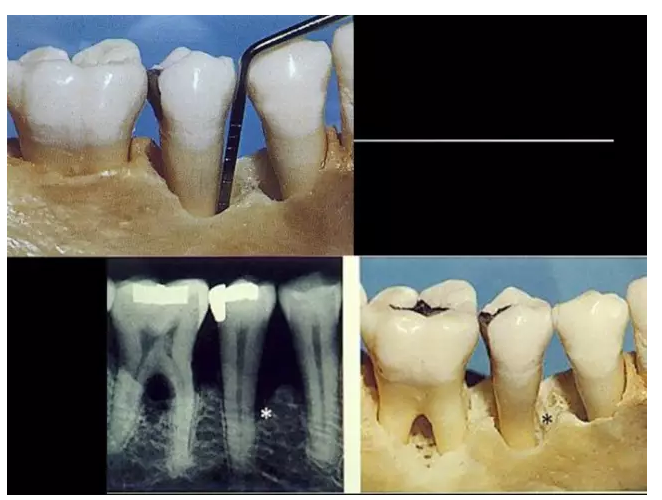

相關(guān)牙周防治